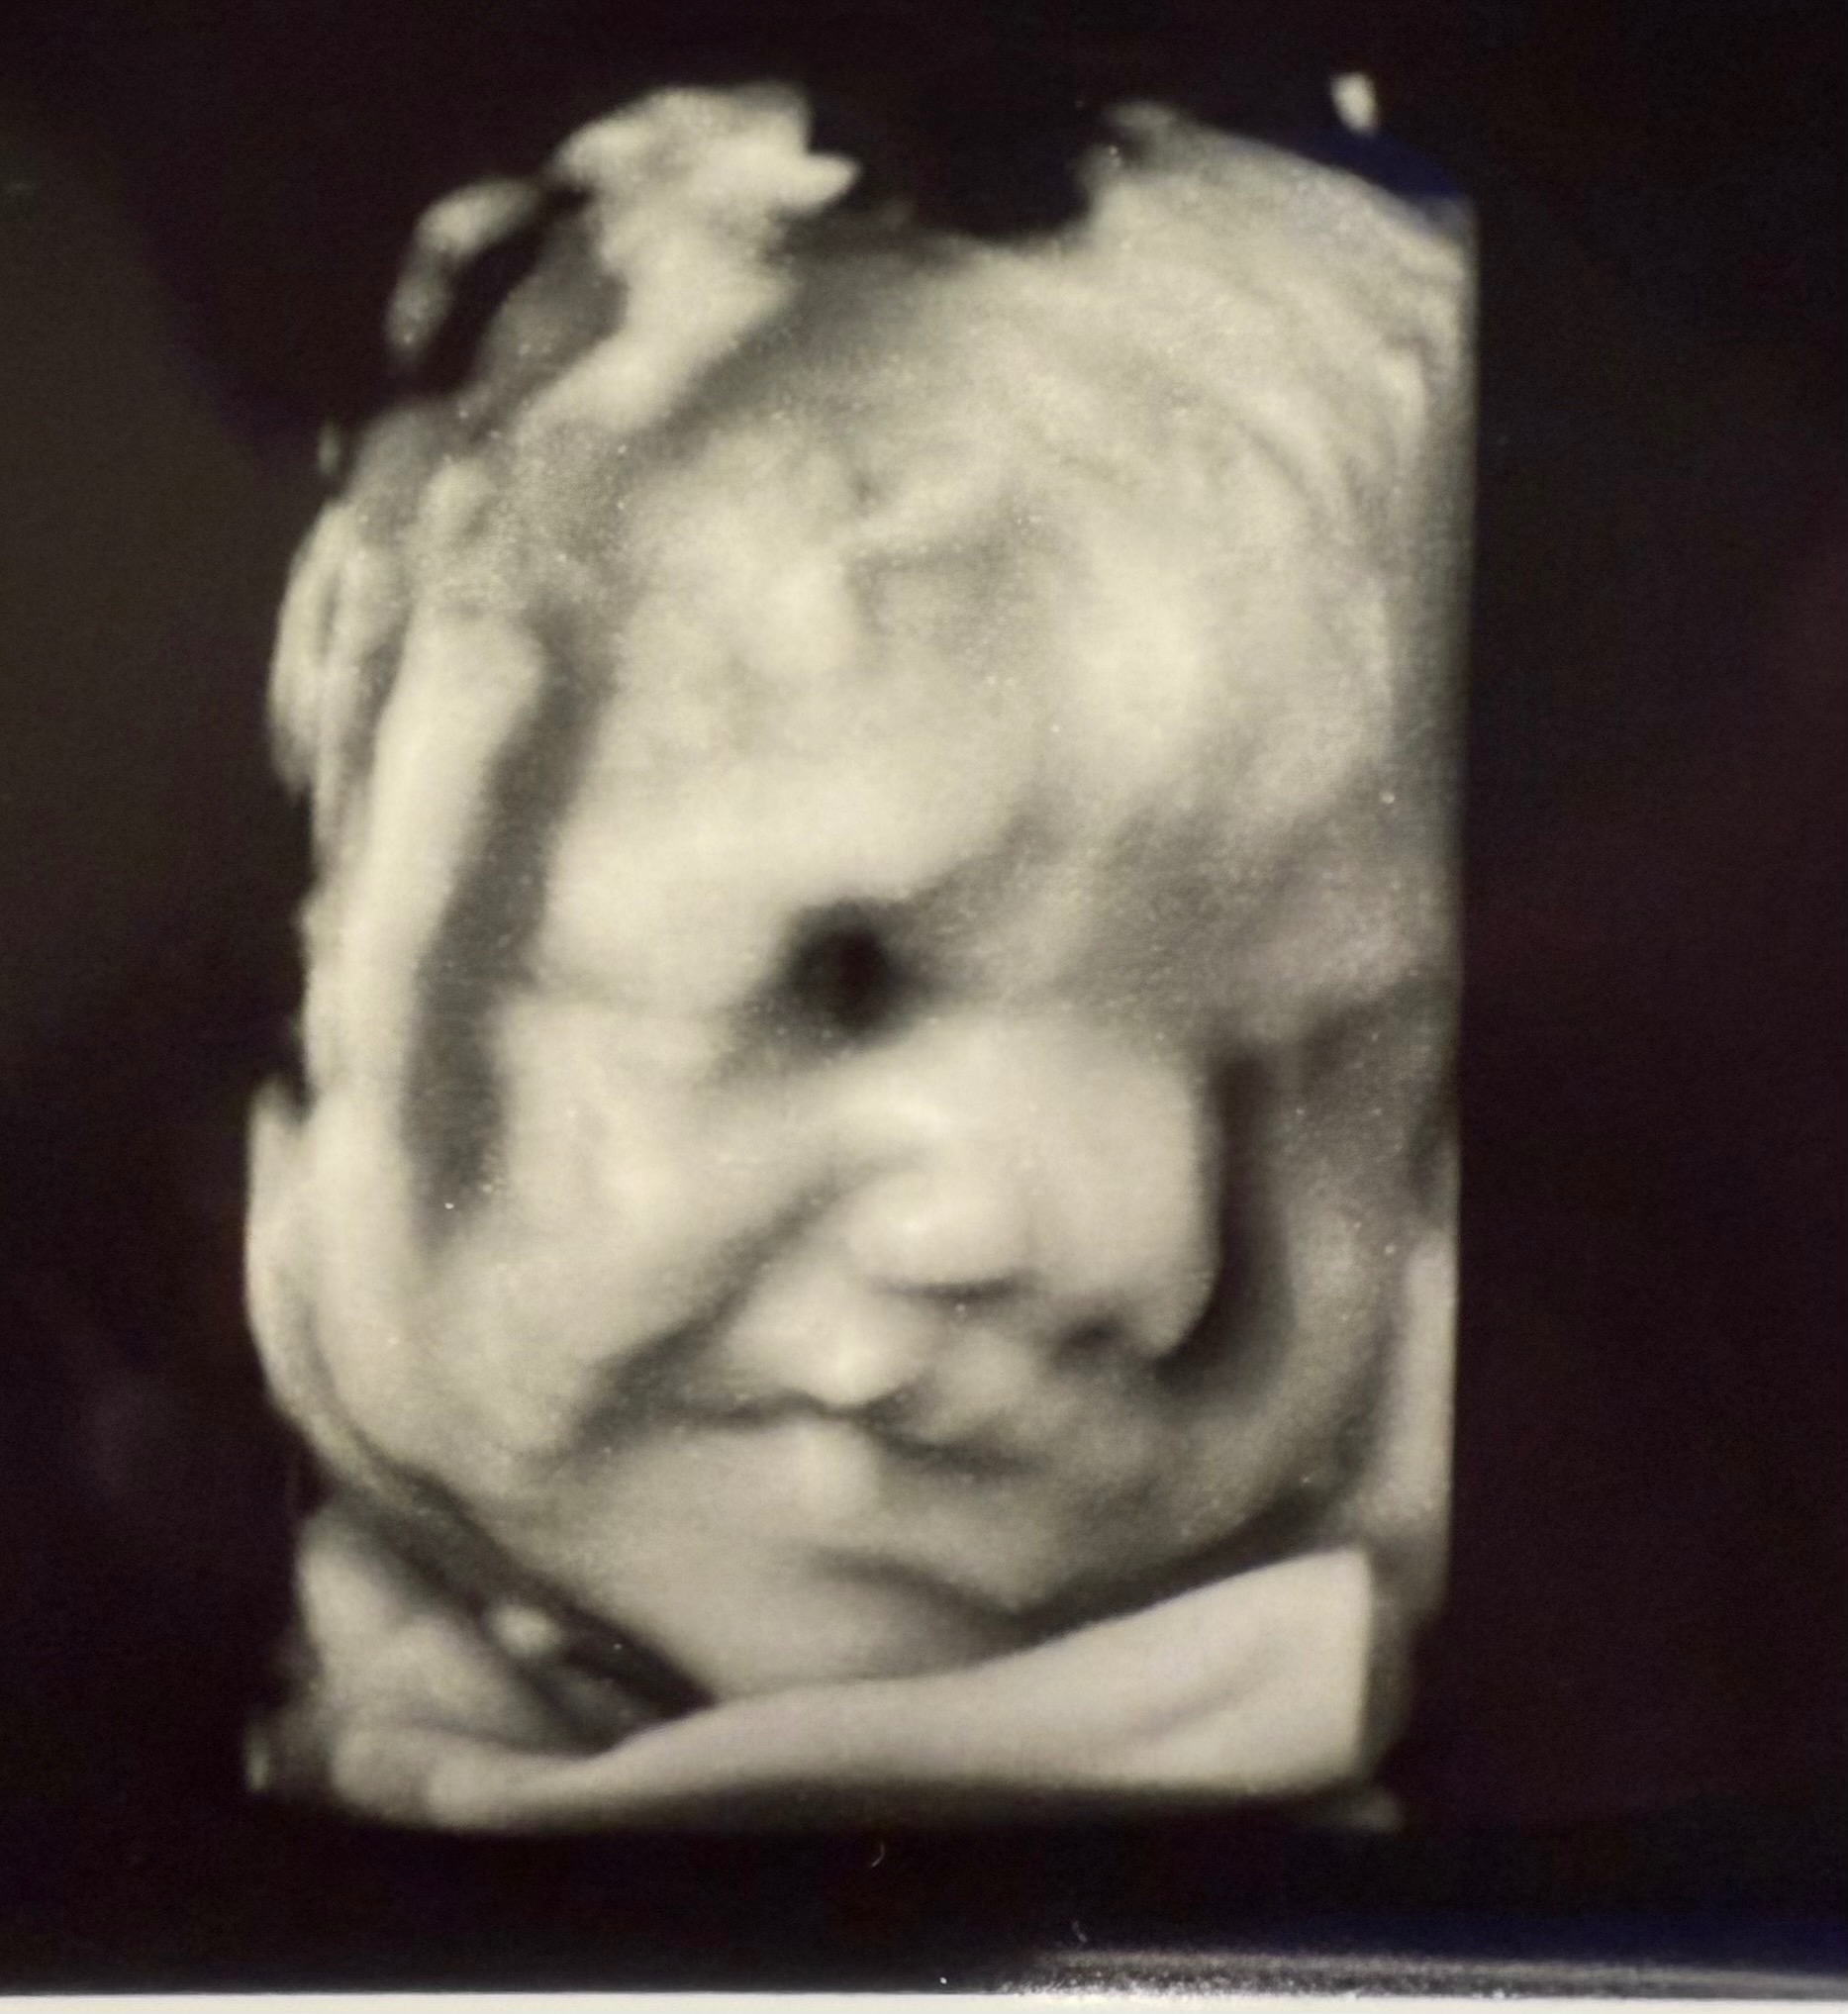

She and her husband, Edgar, are expecting their first child, sweet baby girl, Valentina. She is already so deeply loved, and we are trusting for strength, healing, and provision every step of the way. I created this GoFundMe to support them as they prepare for the medical care, surgeries, and unknowns ahead.

Valentina has been diagnosed with several complex congenital heart and organ conditions. She has Hypoplastic Right Heart Syndrome (HRHS), meaning the right side of her heart is underdeveloped. She also has Double Outlet Right Ventricle (DORV), where both major arteries come from the right side of her heart instead of being properly separated.

In addition, Valentina has Pulmonary Stenosis (PS), which means the pathway to her lungs is very narrow, making it harder for blood to flow properly.

She has also been diagnosed with heterotaxy syndrome, a condition that affects how her organs are arranged. Her stomach is on the right side, her liver sits in the middle, her intestines are rotated, and she does not have a spleen, which can affect her immune system.

Because of these conditions, Valentina will need at least two major heart surgeries, one around 3 months old and another around 3 years old, to help correct the “plumbing” of her heart and improve how it functions.

Immediately after birth, she will be transferred to the pediatric cardiac care unit at Children’s Hospital. There, doctors will perform genetic testing, an MRI, and evaluate whether her pulmonary veins are properly connected to her heart. Depending on what they find, she may need emergency surgery right after birth.